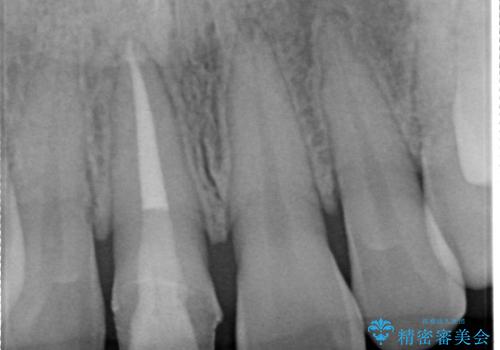

- 仮歯で矯正治療を行い、治療終了したためセラミックにて最後仕上がりをきれいにされたいという患者様の症例です。

矯正の時使用していた仮歯を新調し、その後最終的な形を作ってから型取りを行います。